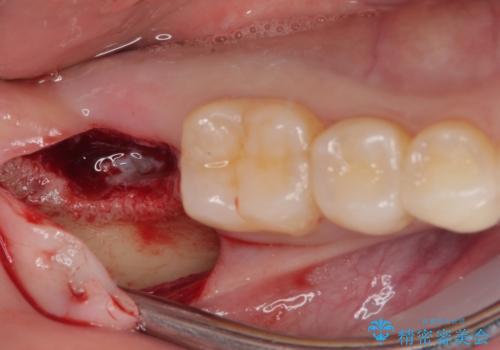

インプラント埋入と同時に仮歯を装着するために、事前に仮歯を用意し、速やかにインプラント埋入を行うこととしました。

抜歯された骨の穴は、インプラント埋入時にはまだ大きな窩洞となっていましたが、径の大きいワイドインプラントを選択することで、埋入時に十分な安定を獲得することができました。

後方には欠損が残っていたため、補填材を填入しました。

術後にインプラントが骨から脱落することがありますが、特筆するトラブルなどなく、最短の3ヶ月で治療を終えることができました。